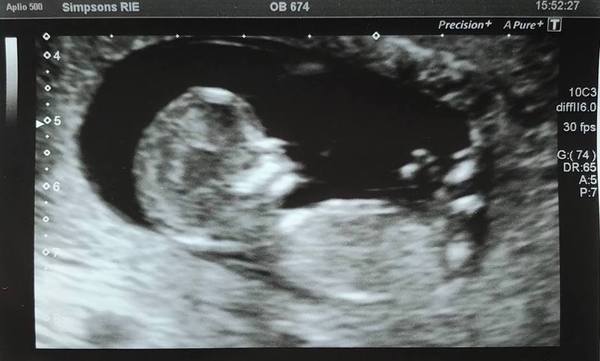

Had 12 week scan last Thursday, right on 12 weeks, all well. Here's a pic in case anyone would like to see! I wish I could look in there all day, it was so the best pay off for all the worry - he/she wouldn't keep still so pics were a bit tricky. We desperately don't want to actually know the sex but I was a demon at speculating nubs and skulls and so on, clearly have no self control! Then a bus drove into us on the way home (all absolutely fine, except for poor car).

That’s a lovely clear scan picture!

@PassTheAfterEights Omg beautiful scan picture! I am so happy to see it. Congratulations. Also glad you're all ok following the car accident.